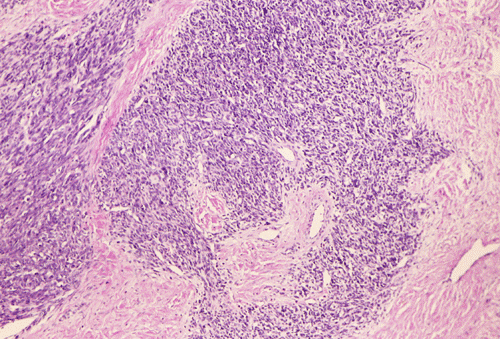

At low power magnification (Panel A and B), the tumor seems to have two distinct components. The first is a highly cellular, basophilic, background stroma. The second is islands of well-demarcated, pale bluish chondroid, hypocellular areas reminiscent of hyaline cartilage. Together, these two components impart a so-called "white clouds in blue sky" histologic appearance. At medium- and high power magnification (Panel C and D), the lacuna in the chondroid areas are well appreciated which helps to confirm the cartilaginous nature of these pale islands. Please note the impressive nuclear pleomorphism in the neoplastic chondrocytes (Panel D).

The basophilic background is composed of tightly packed, undifferentiated spindle cells without significant deposition of collagen fibers in between (Panel E). Panels  F, G, and H are taken from a different area of the tumor and were not posted on the question web-page. The pathologic change in these areas are very common among mesenchymal chondrosarcoma and should be looked. These include lobules of highly cellular tumor separated by fibrous connective tissue septa (Panel F) and Prominent tumor vascularity with highly branching vessels which (with a bit of imagination!) resemble deer "antlers" or "staghorns"(Panel G and H). This pattern of vessel distribution is similar to that seen in hemangiopericytoma (an uncommon soft tissue tumor) and is therefore often described as a “hemangiopericytoma-like” vascular pattern. The overall gross and light microscopic features in this case are consistent with a diagnosis of primary extraskeletal mesenchymal chondrosarcoma.

Grossly, mesenchymal chondrosarcoma typically appears as a circumscribed, lobulated, solid mass with a soft, fleshy, grey-white to gray-pink cut surface. Scattered deposits of cartilage and/or bone of varying size may be grossly recognized, and areas of hemorrhage and necrosis may be present. Tumor size is variable with reported tumor diameters ranging from 3 - 37 cm. Microscopically, mesenchymal chondrosarcomas are biphasic tumors composed of sheets of round to spindle-shaped primitive mesenchymal cells surrounding discrete islands of hyaline cartilage. The proportions of primitive and cartilaginous elements vary widely among tumors and even within different areas of the same tumor. Cartilaginous differentiation ranges in degree and extent from small foci with high-grade nuclear features to large areas of well-differentiated cartilage. The primitive mesenchymal component is highly vascular, typically containing large numbers of highly branched vascular channels (the so-called “hemangiopericytoma-like pattern”).